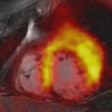

PET/MRI offers details in acute myocardial infarction cases

January 9, 2014